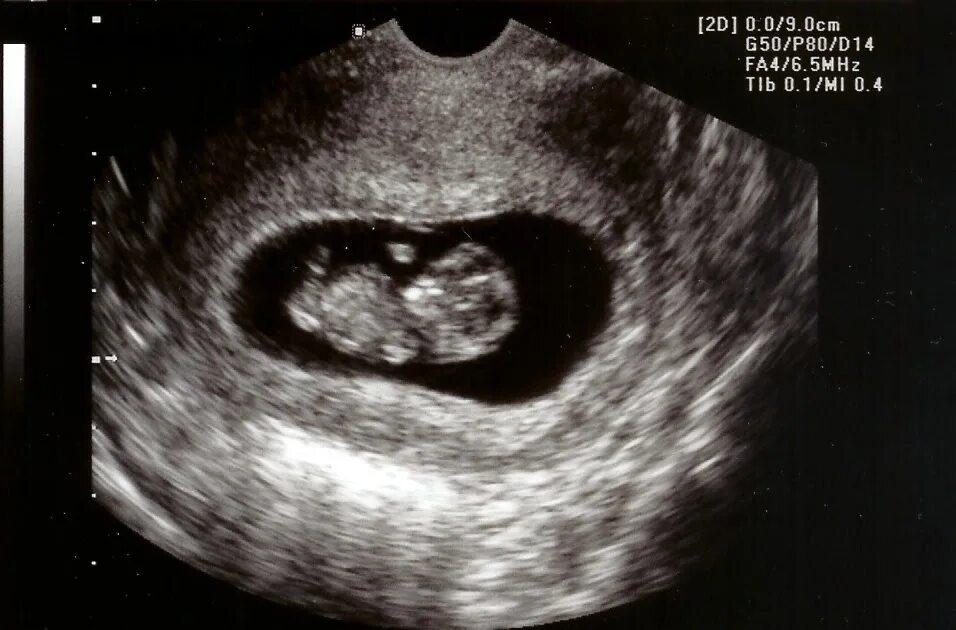

1 9 неделя беременности